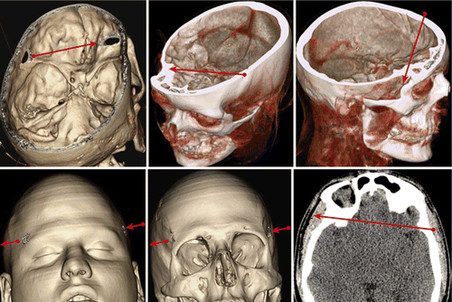

Ученые, специальностью которых является, как ни странно, не история, а неврология и хирургия, прежде всего занялись вопросом о том, каким образом Михаилу Кутузову удалось выжить после двух пулевых ранений в голову, которые по всем показателям должны были оказаться для него смертельными. Первую рану полководец получил 23 или 24 июля 1774 года во время Русско-турецкой войны в сражении у деревни Шумы рядом с Алуштой. Пуля вошла в левый висок и вышла из правого, по сути, пронзив голову насквозь. Результатом ранения стало косоглазие, но зрение Кутузова сохранилось.

Реконструкция траектории первой пули, ранившей Кутузова. Neurosurgical Focus

18 августа 1788 года в сражении под Очаковом Кутузов был ранен снова. На этот раз пуля вошла в левую щеку и вышла сзади, под основанием черепа. Если после первой травмы полководец восстанавливался довольно долго, уезжая лечиться в Германию, то на восстановление во второй раз ушло всего четыре месяца, после чего Кутузов вернулся к военной службе. Оба раза операции проводил служивший в русской армии француз Жан Массо.

Реконструкция траектории второй пули, ранившей Кутузова. Neurosurgical Focus

Ученые восстановили траекторию пуль, пробивших череп полководца. Оказалось, что первая из них, помимо того что разрушила кость глазницы, повредила лобную долю головного мозга, которая отвечает за способность человека принимать решения. По мнению исследователей, именно это стало причиной решения оставить Москву на разорение французской армии: мозг полководца просто не позволил ему поступить более решительным образом.